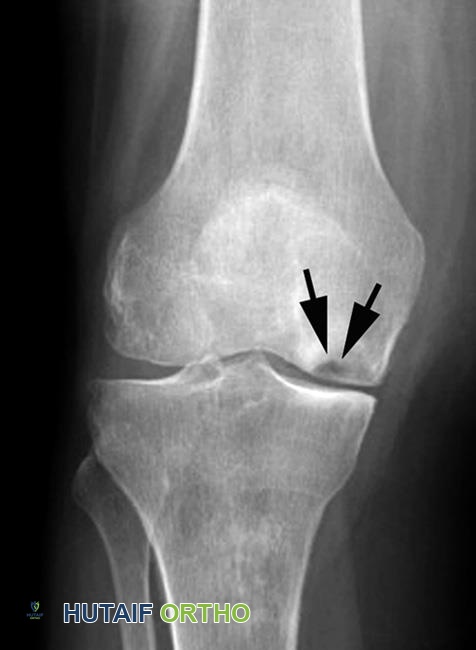

متلازمة ألم الرضفة الفخذية ركبة العدّاء الأسباب التشخيص العلاج والتعافي مع الدكتور محمد هطيف في صنعاء

دليلك الشامل لمتلازمة ألم الرضفة الفخذية (ركبة العدّاء) في صنعاء. تعرف على الأسباب، الأعراض، التشخيص، خيارات العلاج غير الجراحي والجراحي، وب…